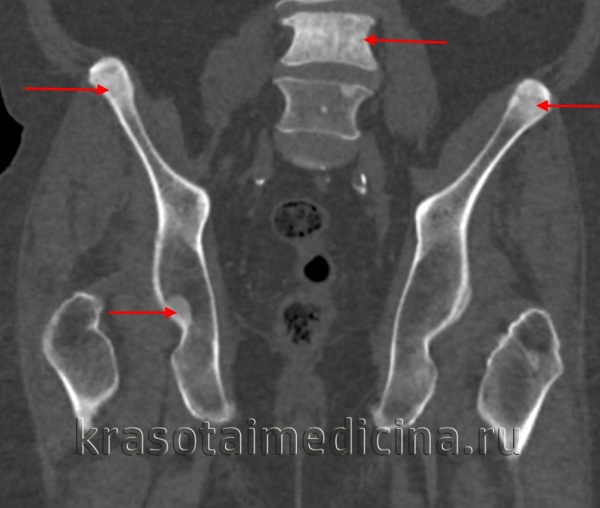

Пикнодизостоз

Пикнодизостоз наследуется по аутосомно-рецессивному типу, обычно манифестирует в раннем возрасте. Выявляется значительное отставание в росте. Лицо пациента имеет характерный вид: угол нижней челюсти расширен, лобные бугры увеличены, нос клювовидной формы, определяется гипертелоризм. Развитие зубов нарушено. Отмечается выраженное укорочение кистей в сочетании с гипоплазией дистальных фаланг пальцев. Часто наблюдаются патологические переломы. На рентгенограммах обнаруживается распространенный остеосклероз, наиболее ярко выраженный в дистальных отделах конечностей.